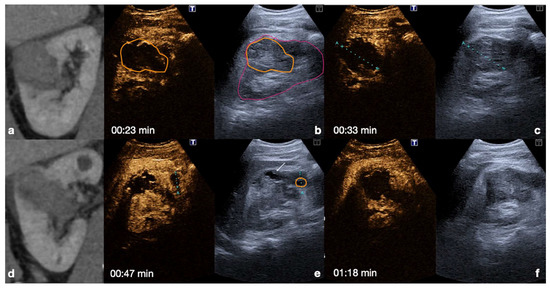

2.2.2. Follow-Up of Conservatively Managed Abdominal Trauma

In follow-up CEUS examinations, the known injured organ is targeted, and all contrastographic phases are evaluated to exclude any contained vascular lesions in the arterial phase. Any regression of the parenchymal injured area is monitored during the venous and late phases [13]. In the event of any worsening changes in the post-traumatic findings, the use of MDCT with intravenous iodinated contrast medium administration is mandatory for the same reasons as above (Figure 9).

Figure 9.

CEUS follow-up.